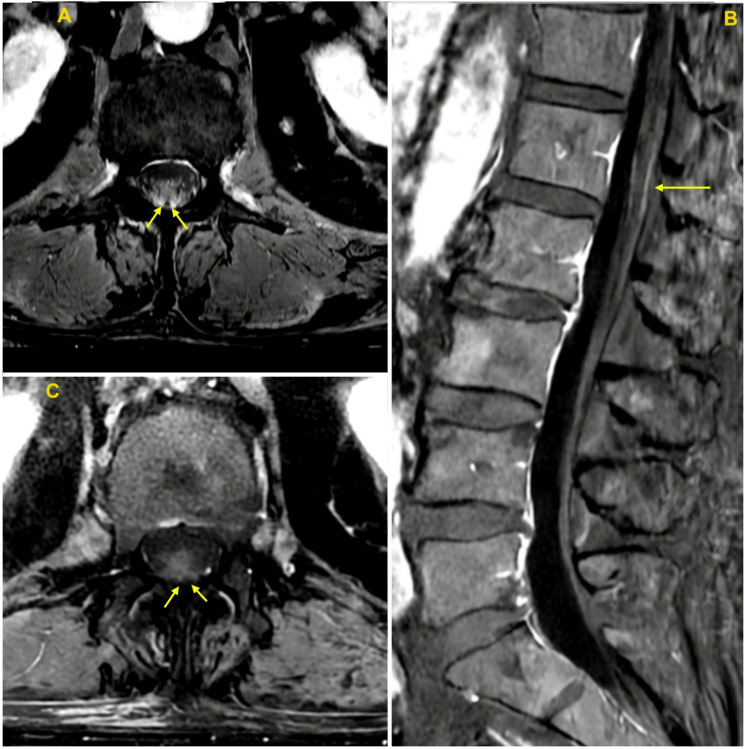

Case presentation: A 74-year-old man presented with acute dysarthria and ophthalmoparesis, which rapidly progressed to quadriparesis and respiratory failure requiring intubation. Magnetic resonance imaging (MRI) revealed thickening and enhancement of the cauda equina nerve roots. Due to high clinical suspicion for botulism, heptavalent botulinum antitoxin was administered. Intravenous immunoglobulin was also given, as the imaging findings raised concern for an alternative diagnosis of Guillain-Barré syndrome (GBS). Blood and stool samples later tested positive for BoNT type A, and C. botulinum was isolated from the stool, confirming AITB. The patient experienced a gradual but prolonged recovery of motor function following treatment.

Conclusions: Botulism in both infants and adults is not typically associated with abnormal neuroimaging findings. To our knowledge, this is the first reported case of cauda equina nerve root thickening and enhancement on MRI in AITB-or in adult botulism more broadly. We outline the differential diagnosis, pathophysiology, and treatment of botulism. This case underscores that abnormal neuroimaging should not delay prompt empiric treatment for botulism when clinical suspicion is high.